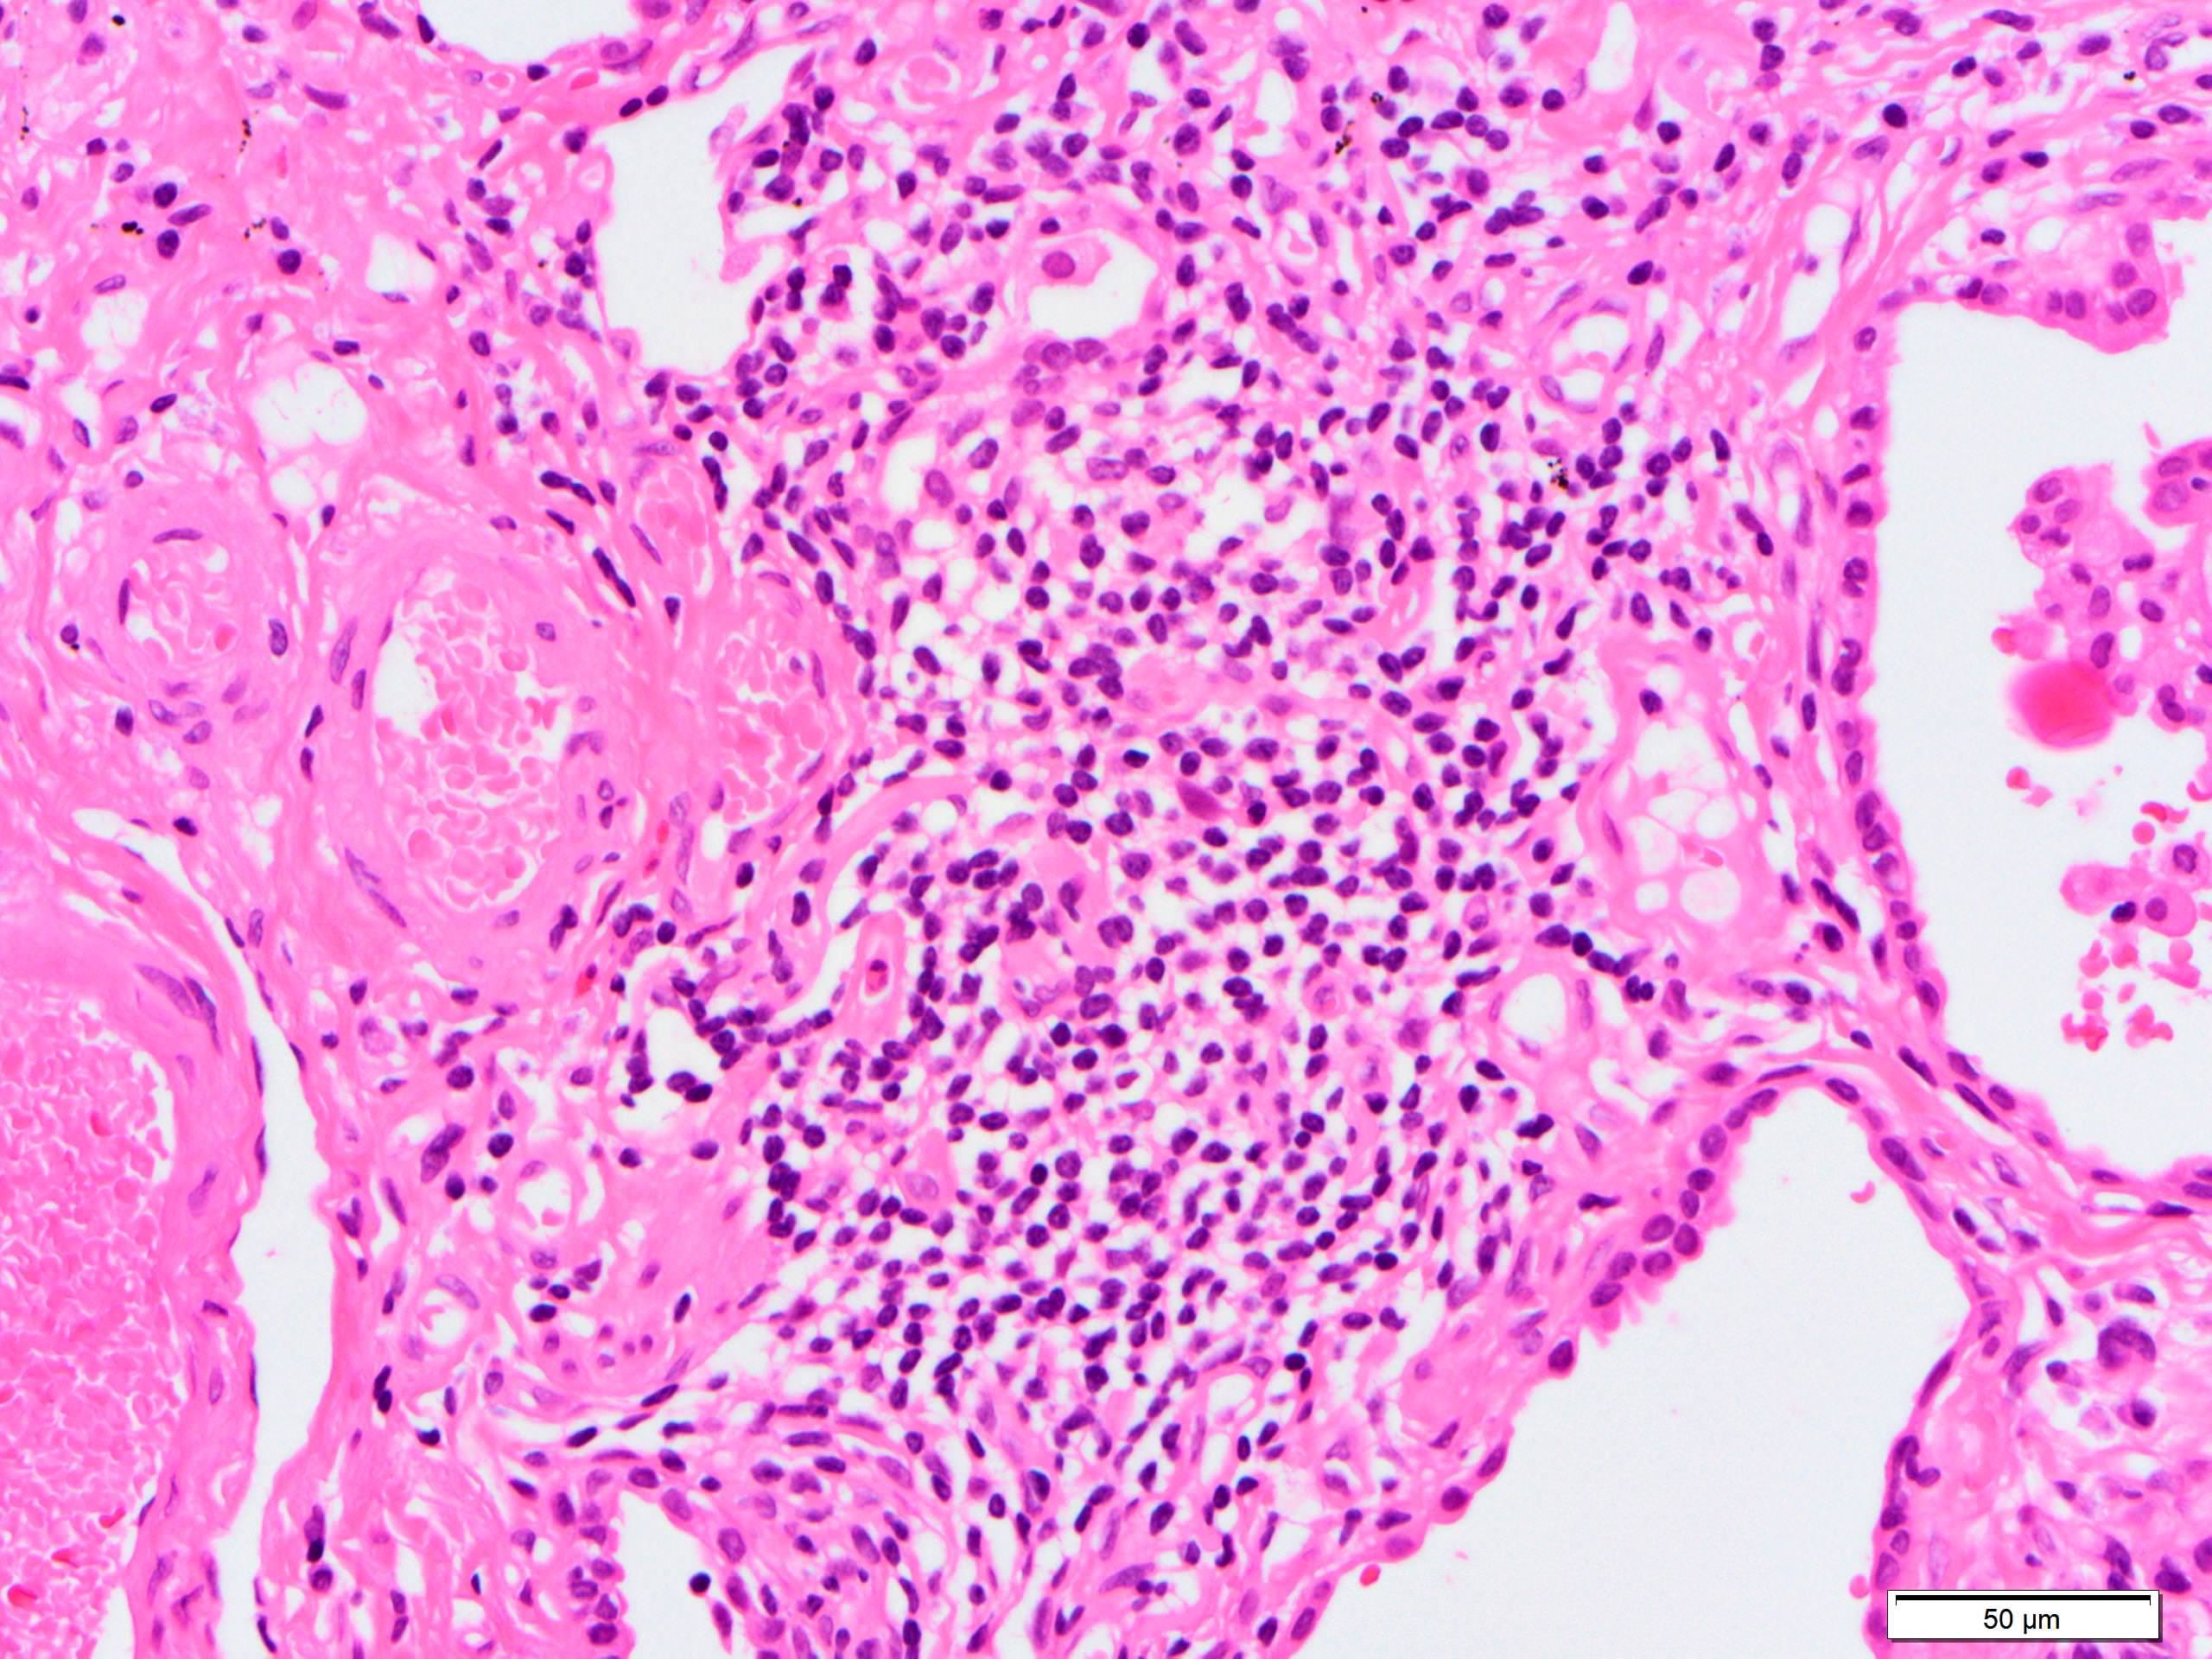

Microscopic (histologic) description

- Since there are few specific findings for NSIP pattern, it is essential to exclude other lung diseases on histology (Am J Respir Crit Care Med 2008;177:1338)

- Characteristic findings of NSIP pattern

- Diffuse and uniform inflammation ("temporal homogeneity") on low power of alveolar wall, bronchovascular bundles and pleura

- There are usually no normal alveolar walls in the affected lobules

- Cellular or fibrotic change

- Lymphocytic or plasmacytic infiltration

- Loose fibrosis

- Lung architecture is frequently preserved

- "Cellular NSIP" or "fibrotic NSIP" can be stated specifically in pathologist report

- Diffuse and uniform inflammation ("temporal homogeneity") on low power of alveolar wall, bronchovascular bundles and pleura

- Features of interstitial pneumonia with autoimmune features (IPAF) (Chest 2010;138:251):

- Lymphoid aggregates with germinal center

- Extensive pleuritis

- Prominent plasmacytic infiltration

- Dense perivascular collagen

- It is quite rare to see pure NSIP on histology - typically there are focal findings of other interstitial lung disease (Histopathology 2014;65:549)

Microscopic (histologic) images

Contributed by Akira Yoshikawa, M.D.

Contributed by Akira Yoshikawa, M.D.